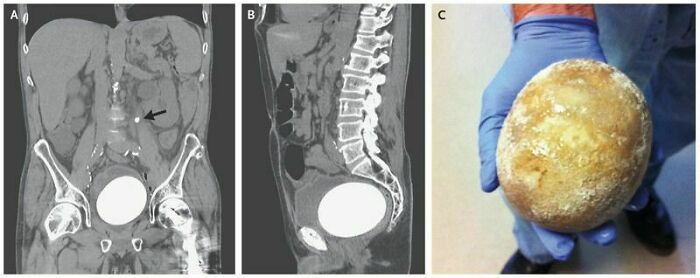

My Husband Suffers Frequent Kidney Stones. He Just Passed This Nightmarish Thing

Ouch. Women often say, there's no more physical pain than giving birth vaginally but a woman friend who has giving birth AND had a kidney stone passing told me the kidney stone pain hurt more, actually. (I have no personal experience with kidney stones and only a C-section, so don't lecture me, I'm just passing along her experiences)

Neobladder Stone